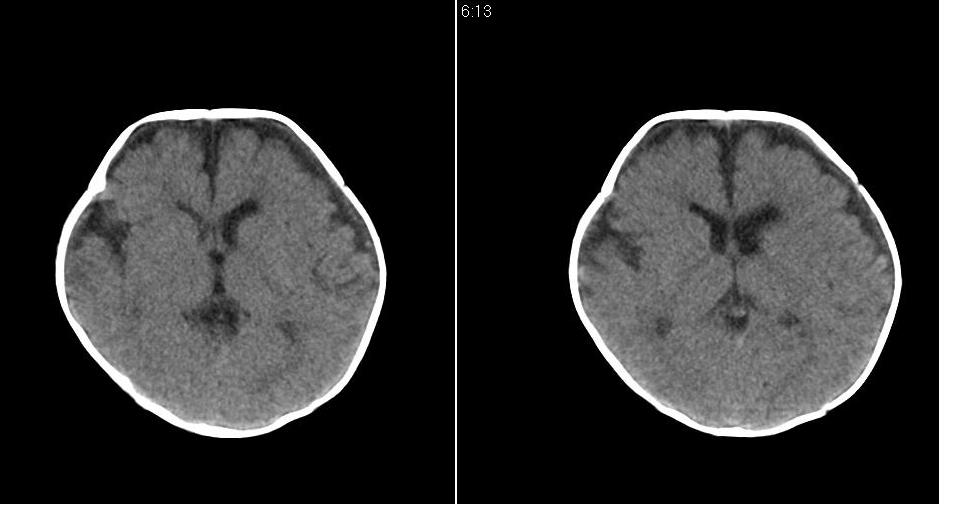

标题: PED1744:颅脑CT平扫

男 3个月,头大,颈软,头向后仰。

外部性脑积水

考虑外部性脑积水。

脑外间隙增宽,未见明显异常。

脑外间隙增宽,余未见明显异常。

脑外间隙增宽,现在好像有人说是一种发育性的交通性脑积水

蛛网膜增宽,外部性脑积水?

外部性脑积水(也就是诸位说的脑外间隙增宽);脑实质内未见异常密度灶,脑室系统无扩张,建议随访,毕竟临床症状听着怪吓人的。